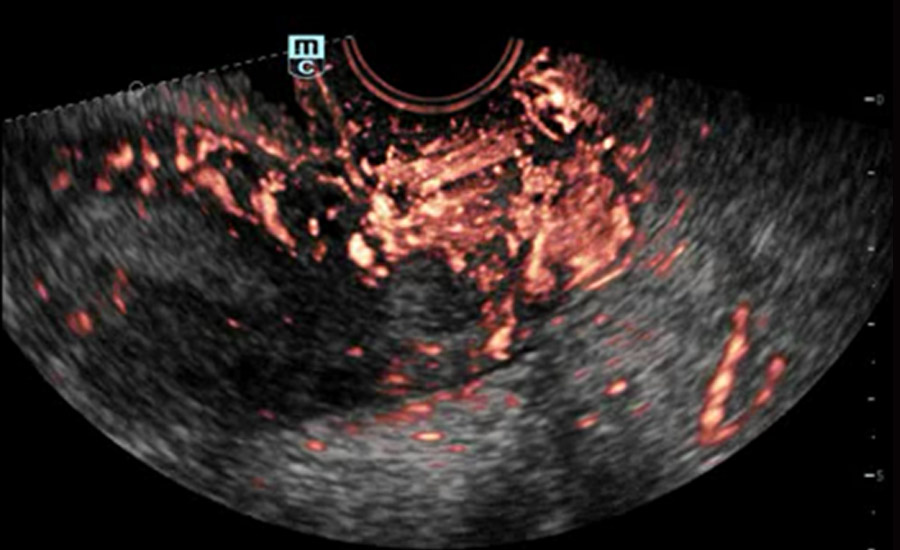

UMA (angiografia ultramicroscĆ³pica)

A tecnologia inovadora elimina as limita??es das tradicionais imagens com Doppler. Com resolu??o espacial e sensibilidade de fluxo ultra-altas, permite a detec??o de perfus?es de fluxos muito sutis e lentos, ampliando assim a aplica??o clĆnica da avalia??o qualitativa e quantitativa do ultrassom no cĆ©rebro fetal, rins, placentas, endomĆ©trios, ovĆ”rios etc.

UMA ā Fluxo renal do feto